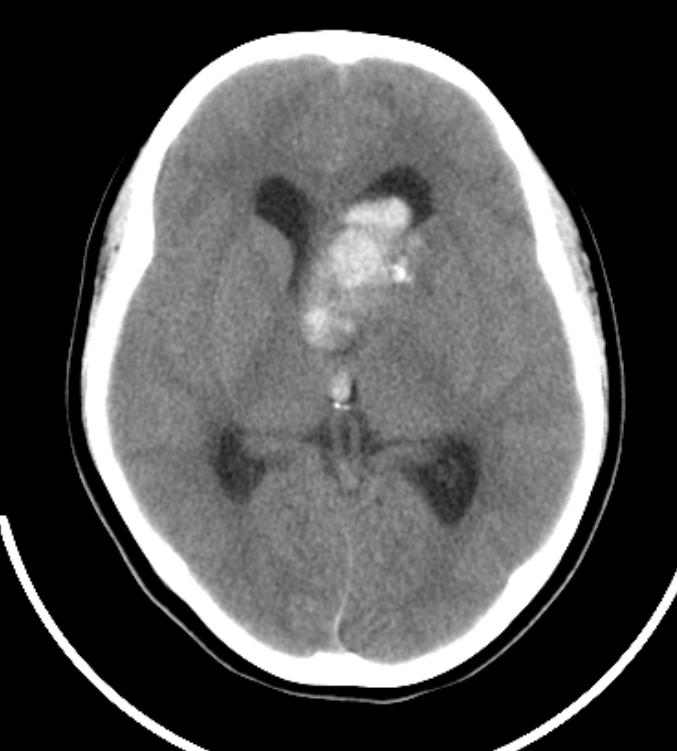

鞍上见一巨大椭圆形、分叶状高、等、低混杂密度肿块,明显占位效应,侧脑室额角、三脑室及四脑室内见高密度区,脑室系统扩大。

鞍上占位,肿块为囊实性,并可见蛋壳样和斑块样钙化。第三、四脑室及侧脑室前角积血,符合颅咽管瘤伴发出血。

鞍上囊实性肿瘤,瘤较大,部分生长于第三、四脑室,并向后推压中脑。其囊壁可见“壳”样钙化,实质部分有不规则斑片状钙化及出血。与周围组织有粘连。因所提供影像不全,故蝶鞍形态不明确,但蝶骨大翼骨质有破坏。

意见:颅咽管瘤,伴出血(出血源于肿瘤脑室部分,顺脑脊液弥散)。

分析:1、鞍上肿瘤表现为囊实性者应首先考虑颅咽管瘤,其余肿瘤,如脑膜瘤、生殖细胞瘤等表现为囊实性是相当罕见的。2、实质部分密度较高,对于颅咽管瘤来说,尚应考虑有钙质沉着和肿瘤内存在较多角蛋白的因素。但因三、四脑室内有高密度影,因而诊断肿瘤伴出血。